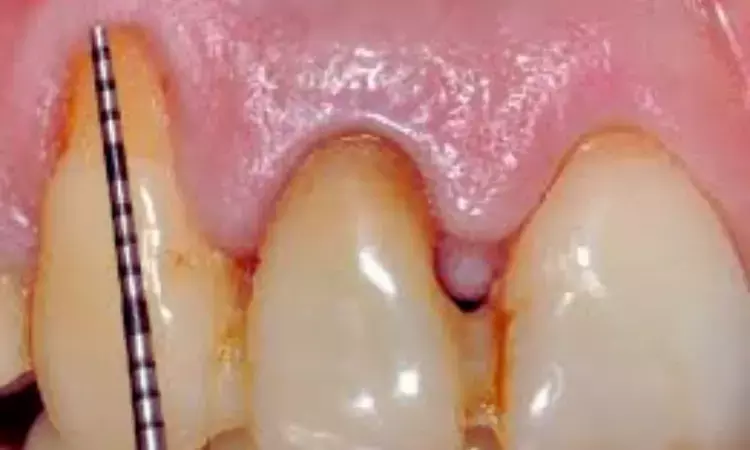

Gingival recession, where the gum margin moves apically and exposes the root surface, is frequently seen in clinical practice. Importantly, nearly half of these cases are associated with NCCLs—tooth structure losses near the gum line that are not caused by decay. When both conditions coexist on the same tooth, they are referred to as combined defects (CDs). These situations are more complex than isolated gingival recession on an intact tooth and often require tailored treatment strategies.

- In cases with mild cervical defects (A−, A+, and B−), evidence indicates that restoration of the non-carious cervical lesion is often not required. Management in these patients can focus exclusively on surgical root coverage.

- The selection of the root coverage technique in mild cases should be guided by the features of the gingival recession and the patient’s gingival thickness.